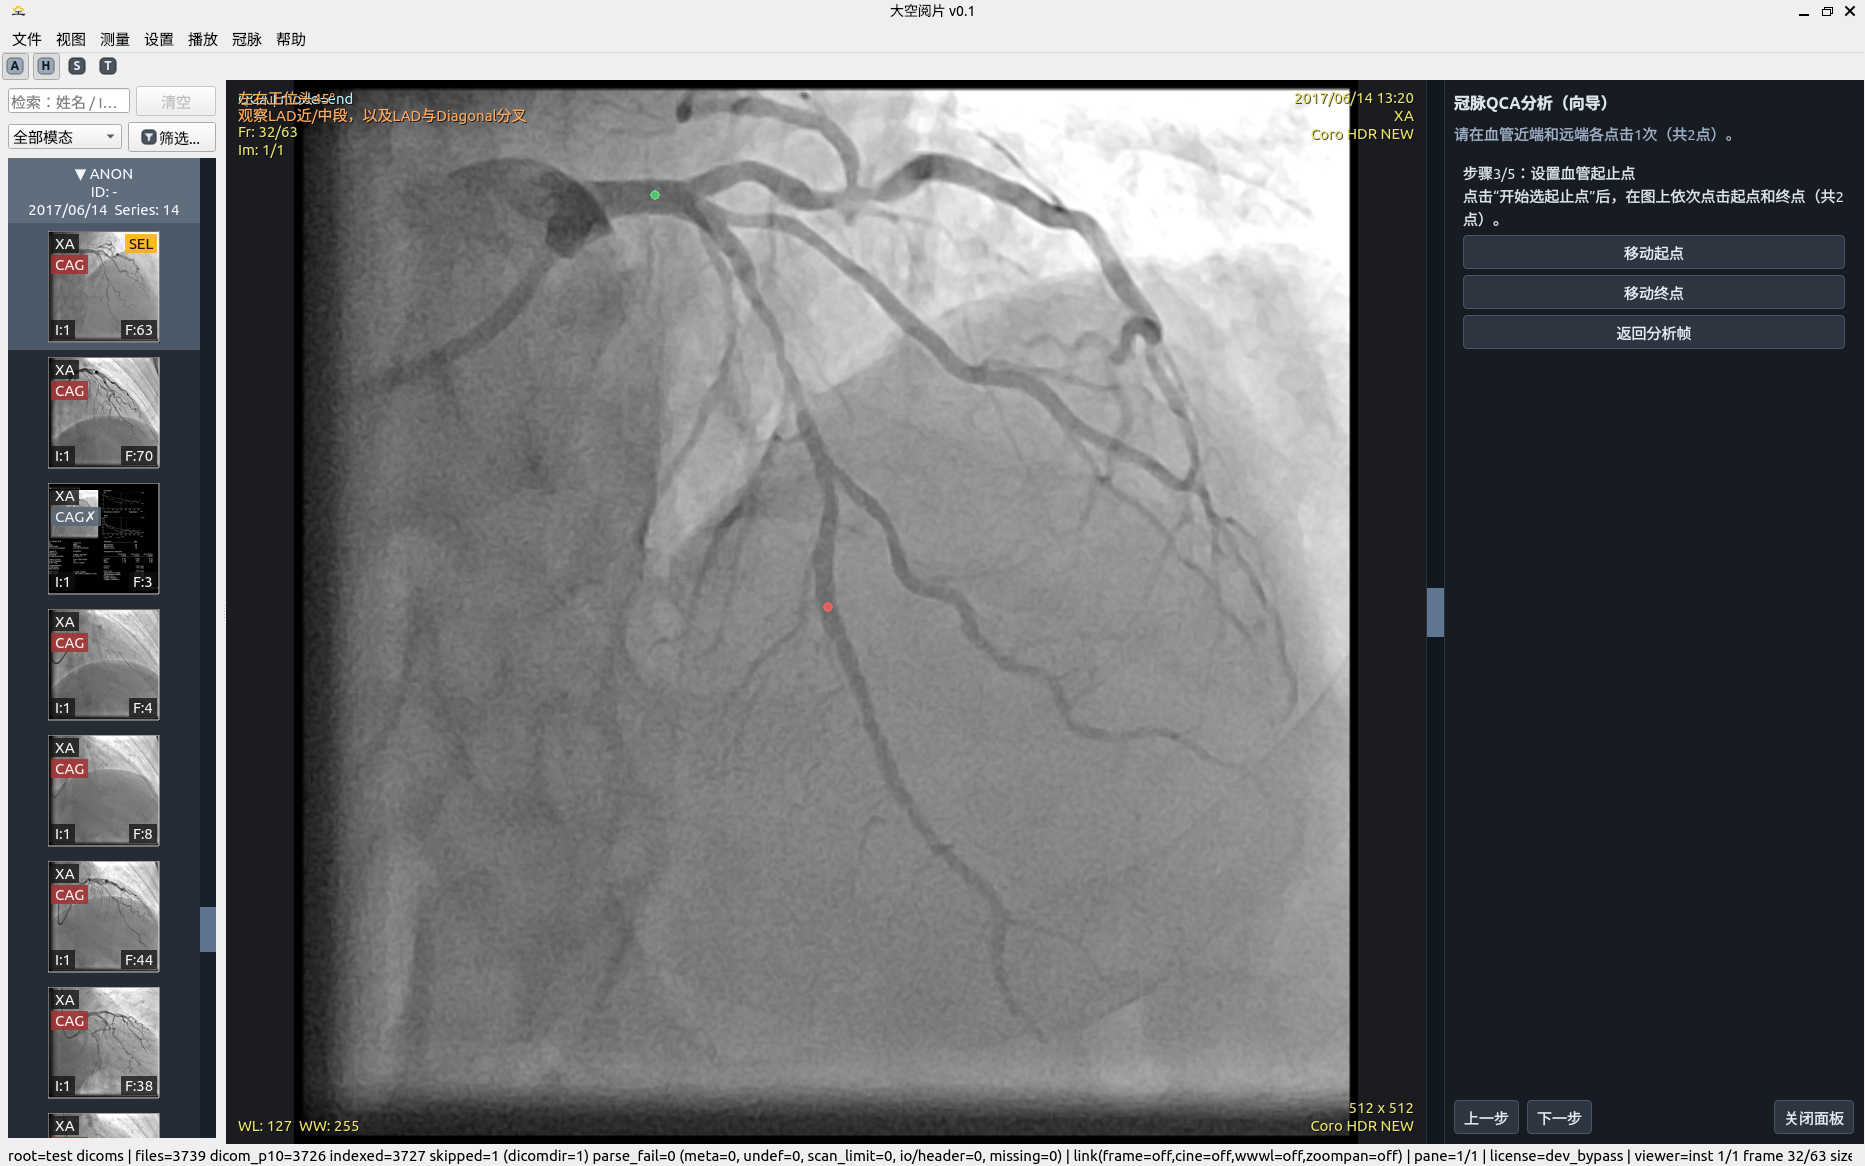

5. 冠脉 QCA 分析

半自动流程强调“可解释 + 可修正 + 可重算”,而非一次性黑盒输出。

• 导管标定:拉直空间剖面 + 左右联合动态规划(DP)+ 亚像素修正。

• 边缘检测:极性自适应 + 有符号边缘特征 + 联合状态 DP + 多峰歧义度。

• 稳健性:MAD 统计、质量等级、结构化告警与恢复建议。

• 几何交叉校验:SID/SOD/ERMF/像素间距参与比例复核。

移动端请按步骤顺序阅读:步骤 1 → 步骤 7。

QCA 分析步骤 1

关键帧选取

QCA 分析步骤 2

导管校准

QCA 分析步骤 3

分析起止点选定